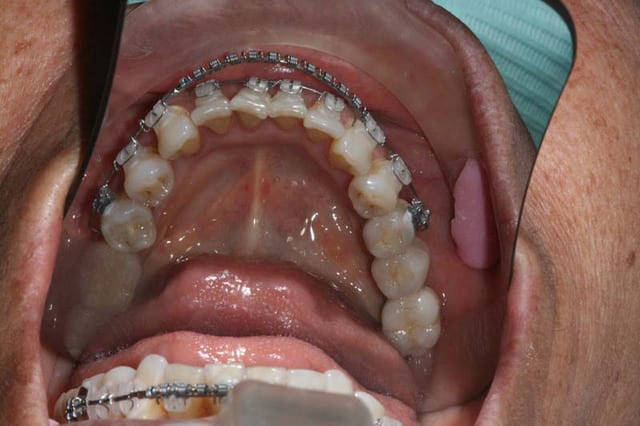

C’est ma préférée

77 ans, un moral d’enfer !

malpositions Inc. Inf. qui déstabilisent son complet du haut

pourquoi, dès qu’on leur fait de la place, 31/41 se mettent à loucher

Une main gauche entiére de décalage annulée par 21,24,25. Regarde bien les pointes des cuspides vestibulaires en 34, 35...

Ces facettes d’usure datent d’avant son complet (7 ans), et peut etre m d’avant son stellite

parceque taper sur 21/24/25 ça va etre difficile